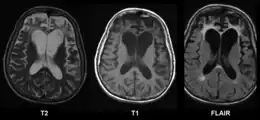

La maladie de Pick est une démence associée à la détérioration des lobes frontaux et temporaux du cerveau. C'est une protéinopathie de la famille des dégénérescences lobaires frontotemporales.